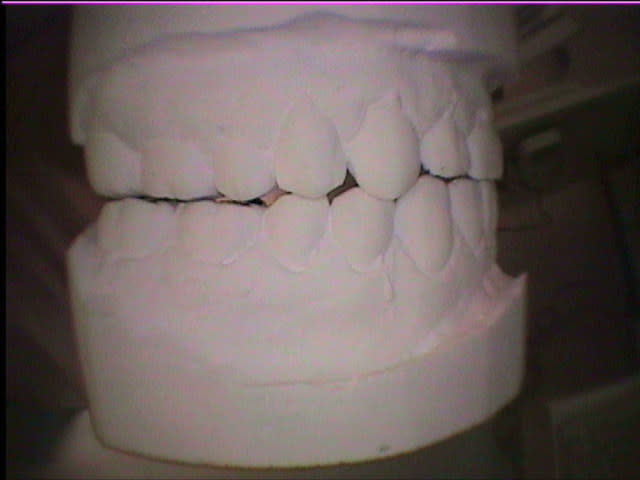

Quelques precisions: peux-tu mettre photo modeles en occlusion face et profils? Afin de voir si décalage mandibule à droite ou à gauche, voir si béances (ou du moins pas de contacts antagonistes), voir rapports dentaires (articulé inversé....).Si y'a des dents traitées précise lesquelles (soins restau, endos, coiffes...).

To pote de 45 berges a une déglutition salivaire atypique (= déglutition infantile chez l'adulte) et tu peux certainement "Augmenter sa DVO" (Voir ce titre dans ce même Forum).

Ceci (dé)montre aussi que ce n'est jamais dans un articulateur que l'on résoud la malocclusion.

Au vu des moulages que tu tiens en occlusion, j'ai de sérieux doutes! Et comment le faire: 2 x 14 ccm? Chirurgie?